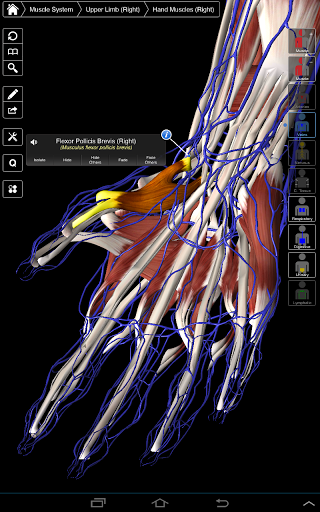

Essential Anatomy 3 reprezentuje najnowsze przełomowe technologie 3D i innowacyjny design. Najnowocześniejszy silnik graficzny 3D, zbudowany na zamówienie przez 3D4Medical od podstaw, zapewnia bardzo dokładny model anatomiczny i zapewnia doskonałą jakość grafiki, której żaden inny konkurent nie jest w stanie osiągnąć.

Aplikacja przedstawia unikalne podejście do uczenia się ogólnej anatomii. Grafika jest nieporównywalna i sprawia, że uczenie się, dzięki wykorzystaniu treści informacyjnej i innowacyjnych funkcji, jest bogatym i wciągającym doświadczeniem.

NOWA TECHNOLOGIA 3D

Essential Anatomy 3 jest responsywny, wizualnie oszałamiający i pozbawiony wysiłku. Aplikacja jest w pełni 3D, co oznacza, że możesz zobaczyć dowolną strukturę anatomiczną w izolacji, a także pod dowolnym kątem.

Mądra funkcjonalność znajdująca się w aplikacji pozwala użytkownikowi usunąć warstwy mięśni za pomocą narzędzia "skalpela". Ta aplikacja zapewnia użytkownikom możliwość włączania / wyłączania systemów bez potrzeby wyłączania poszczególnych struktur lub pomieszania wielu predefiniowanych kart regionalnych, tak jak w przypadku innych aplikacji.

Essential Anatomy 3 został zaprojektowany z myślą o użytkowniku - samo ciało staje się interfejsem. W odróżnieniu od innych aplikacji 3D, które opierają się na wcześniej zdefiniowanych układach anatomicznych i regionalnych rozbiorach, które kierują użytkownikiem, Essential Anatomy 3 3D4Medical pozwala znaleźć to, czego szukasz bez komplikacji.

---- Ponad 4000 bardzo szczegółowych struktur anatomicznych

---- Tryb wielokrotnego wyboru - Ukryj / Zniknij / Izoluj pojedyncze lub wiele struktur

---- nomenklatura łacińska dla każdej struktury anatomicznej